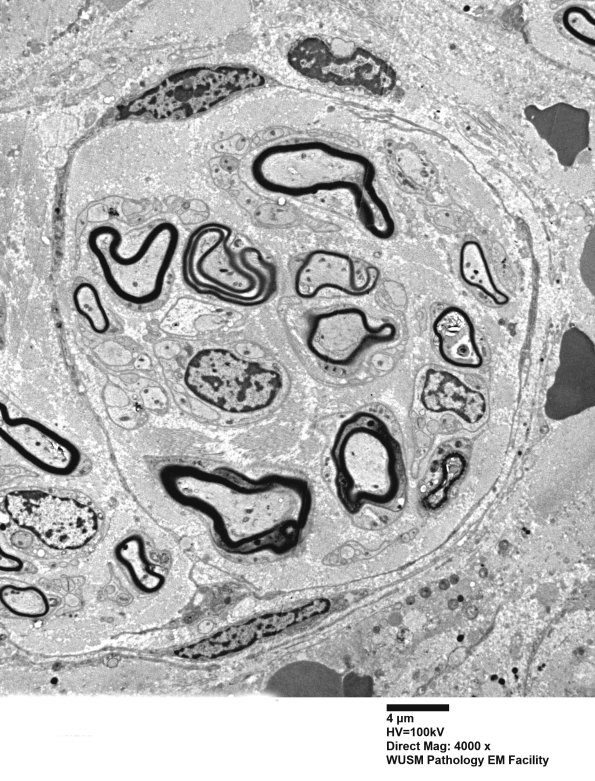

12D1,2 These clusters of axons are surrounded by several turns of spindled cells but compelling basal laminae are not identified. (electron micrographs)